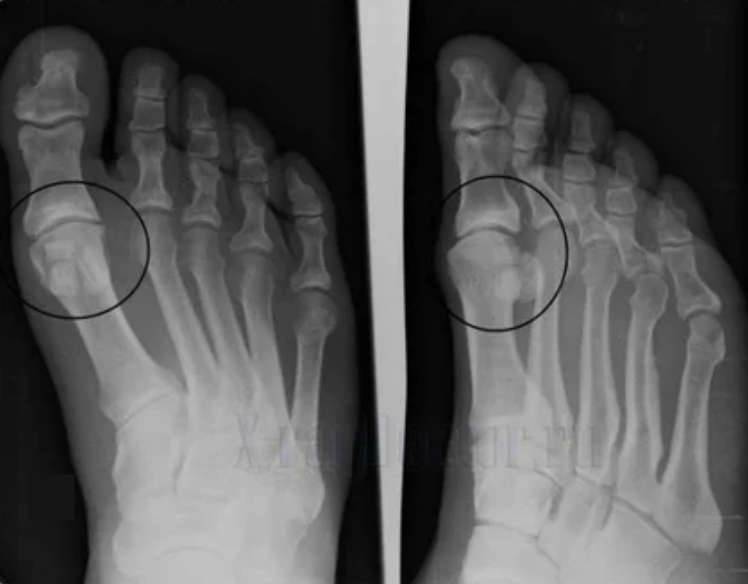

deformacións das extremidades. Aparece nunha forma descoidada da enfermidade, indica a destrución completa do tecido cartilaxe e a aparición de osteófitos. Neste estado, a presión sobre as articulacións enriba e por baixo aumenta, a partir das cales a curvatura pode afectar a toda a extremidade.

É importante lembrar que a deformación dos ósos na perna adoita confundirse co millo. O síntoma é mal perigoso só a primeira vista, pero leva a graves consecuencias.

Para facer un diagnóstico, os reumatólogos estudan as queixas do paciente e prescriben un exame x -ray. Na maioría das veces, a radiografía úsase en 2 proxeccións. O médico mira a presenza de trastornos distóricos en cartilaxe hialina e articulacións óseas. Se a brecha articular é reducida, os ósos están deformados ou aplanados, hai formacións císticas na superficie da cartilaxe, os osteófitos son signos obvios de artrose. Durante a inspección, a artrose indica a inestabilidade da articulación: o eixe das extremidades e a subluxación é perturbado.